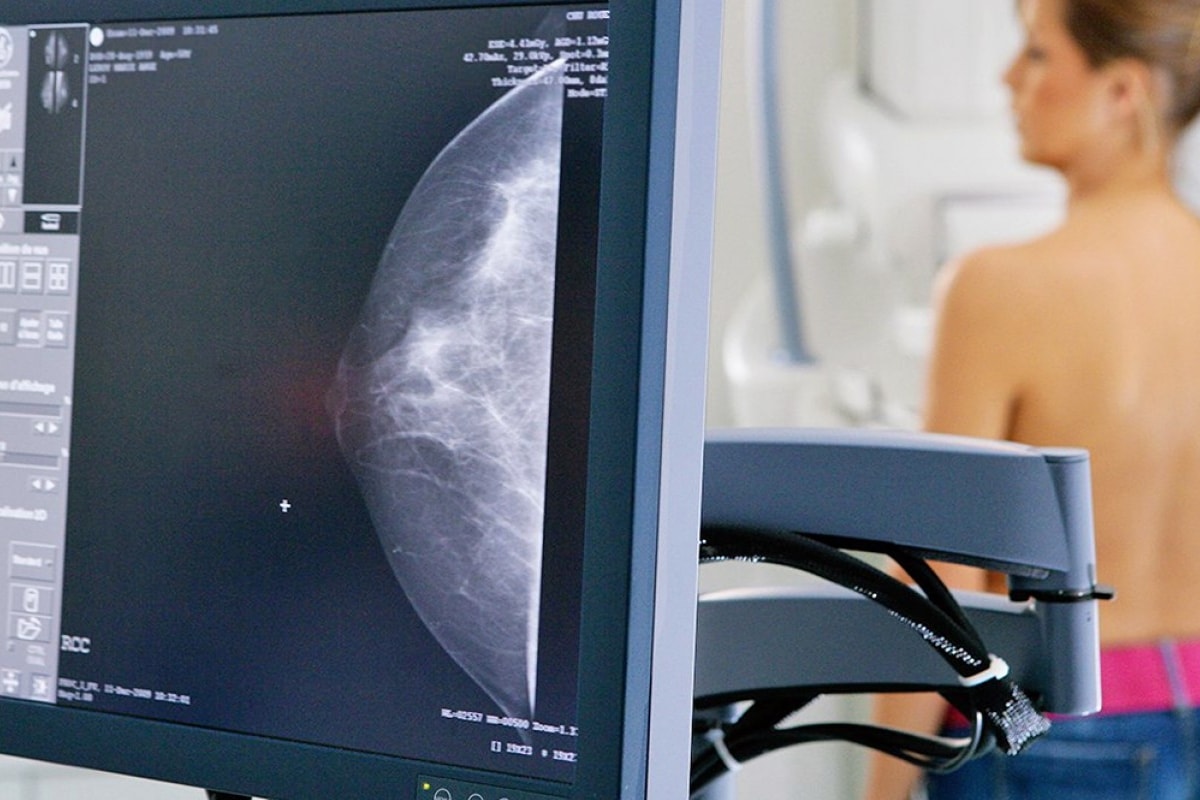

Las microcalcificaciones son hallazgos frecuentes en la mamografía. Aunque generalmente son benignas, algunas veces pueden asociarse con lesiones de alto riesgo de malignidad o cáncer. De acuerdo con su distribución y morfología se les asigna una categoría en el sistema BI-RADS, que el médico a cargo interpretará individualmente para decidir en qué casos se requieren estudios adicionales.

Cuando se detectan calcificaciones sospechosas en una mamografía de control o rutina, puede ser necesario estudiarlas con una mamografía magnificada. La incorporación de la mamografía digital y de la tomosíntesis 3D ha mejorado la evaluación de las microcalcificaciones. Por su parte, la mayoría de las microcalcificaciones no son visibles en la ecografía mamaria, que sí puede aportar otra clase de información complementaria.